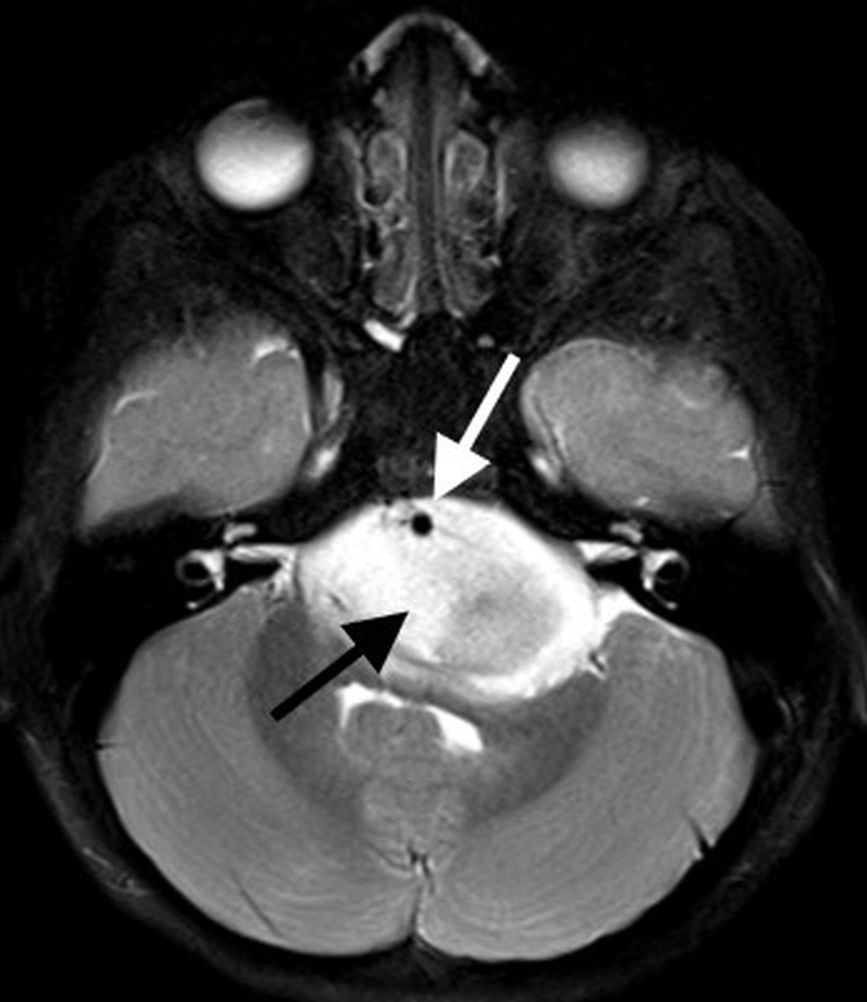

On MR imaging, DMGs present as a diffuse, ill-defined, T2 hyperintense, expansile masses centered within the pons. The degree of enhancement is variable, often absent at initial presentation and typically patchy when present (Fig. 3).

Peripheral enhancement commonly occurs along margins of central necrosis, which occurs more frequently after radiation therapy [25]. Intralesional hemorrhage is uncommon, but areas of hemosiderin deposition may be seen on susceptibility-weighted sequences. Focal areas of restricted diffusion develop in the majority of cases. The presence of central necrosis, diffusion restriction, or enhancement at the time of initial diagnosis has been shown to portend a worse prognosis [24].

Extrapontine spread is common throughout the brainstem, into the thalami and adjacent structures, through the cerebellar peduncles, and into the cerebellar hemispheres. Exophytic components engulf the basilar artery anteriorly and efface the fourth ventricle posteriorly. Disseminated metastatic disease is uncommon, though may be seen occasionally.